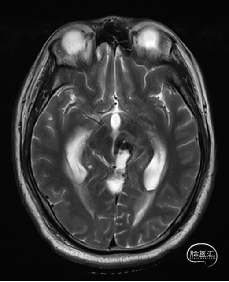

术前MRI检查

术前MRI检查提示左侧丘脑中脑海绵状血管瘤并卒中,梗阻性脑积水;

诊断:1.左侧丘脑中脑海绵状血管瘤并卒中,2.梗阻性脑积水;

年轻患者,较短时间内发生左侧丘脑二次出血,出现右侧面部及上肢麻木,复视,第二次出血后并发梗阻性脑积水,出现头痛。结合病史、神经系统体征、头颅CT及MRI检查,诊断左侧丘脑及中脑CM并卒中、脑积水明确,并导致了神经功能障碍,具备手术指征。

本例患者磁共振检查清晰显示病变位于左侧丘脑中脑区域,且位于丘脑内下方向中脑顶盖延续,病变的上部、前部、外侧部都有重要的神经组织,因此,手术从上方、前方、外侧方向切除病变均难以实施;